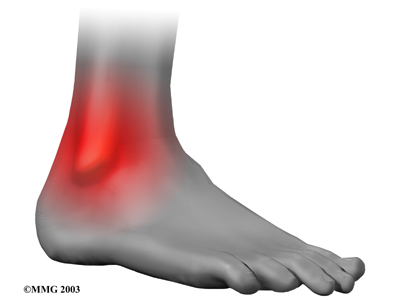

Mild to moderate syndesmosis sprains may at first feel like a routine sprained ankle. Symptoms include pain and swelling on the outside of the ankle.

Outside of the Ankle